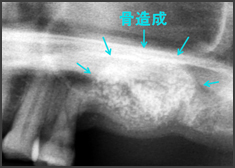

②側方アプローチ法による手術

CASE1

上顎に骨の厚みがありません。

頬骨を取り除き、上顎洞内に付着している粘膜を剥離しています。

約10mmの骨再生ができました

CASE2